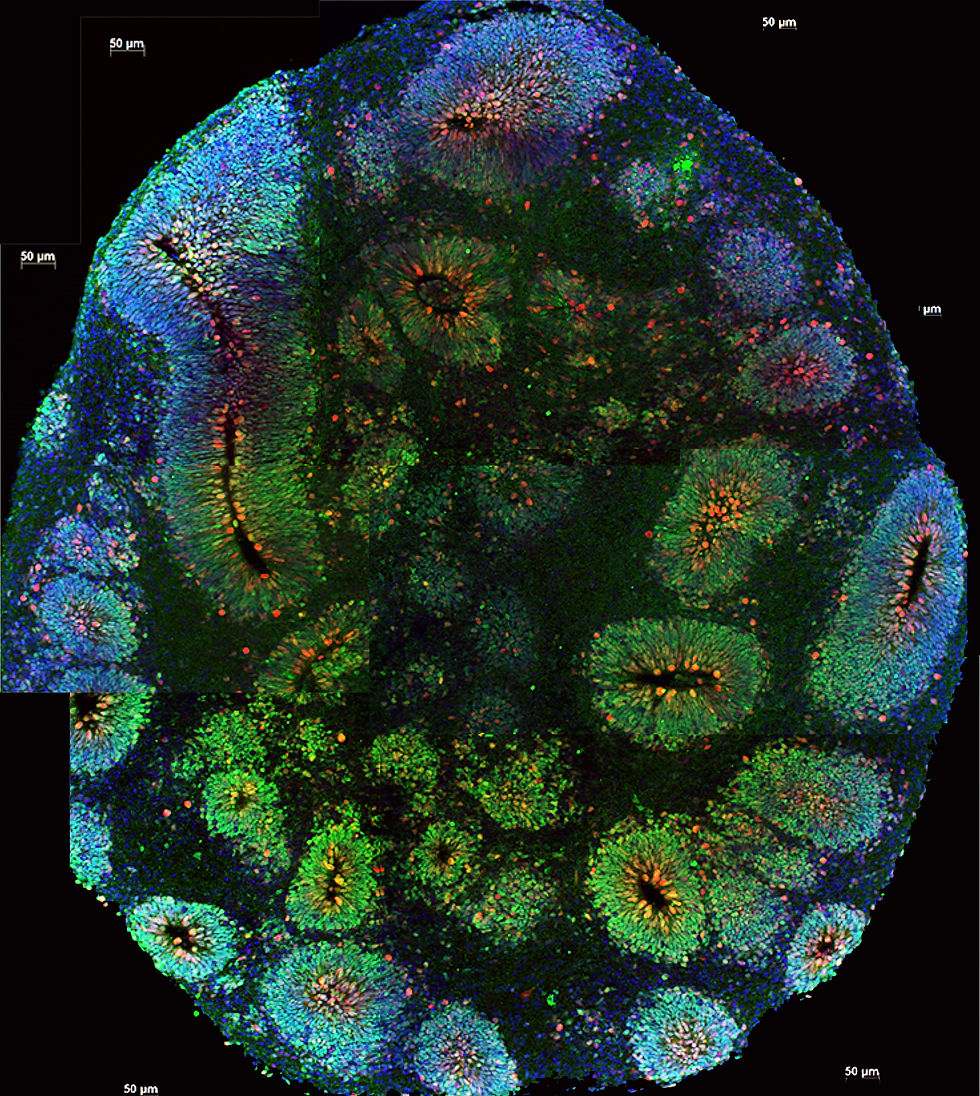

Yoshiki Sasai, Japanese biologist, used the breakthrough of iPSC (induced pluripotent stem cells) to aggregate stem cells into a 3D structure, as opposed to earlier methods which adopted a 2D structure to create organoids. Eventually, Sasai found that when stem cells were put under the proper conditions, they could independently form into their own structures. Flora Vaccarino at the Yale Department of Neuroscience applied this technique in 2012, and her laboratory became the first to create 3D brain organoids. Vaccarino later, using this discovery, created brain organoids meant to model the brain structure of people with autism (Zagorski). The research of 3D brain organoids was furthered in 2013, when the organoids could be created to display representations of multiple regions of the brain (Corró). This allowed researchers to accurately model more complex brain structures. In 2019, Alysson Muotri of University of California in San Diego and his laboratory found that the brain organoids emitted brain waves, similar to those seen in premature babies (Nature).

All organoids are created in labs with the aid of technology. They usually consist of a mix of ESCs and ASCs. The different types of iPSCs are first embedded together to form embryoid bodies. They are then encased in Matrigel, which prevents the bodies from differentiating into specialized cells for the time being (Shou). The structures are then placed within a rotating bioreactor, providing them with a controlled environment to promote tissue and neuronal growth. During this process, the cultures are supplemented with nutrients that push them to form certain structures, in this case, regions of the brain. When not being observed or researched, the organoids are preserved at low temperatures, also known as cryopreservation.